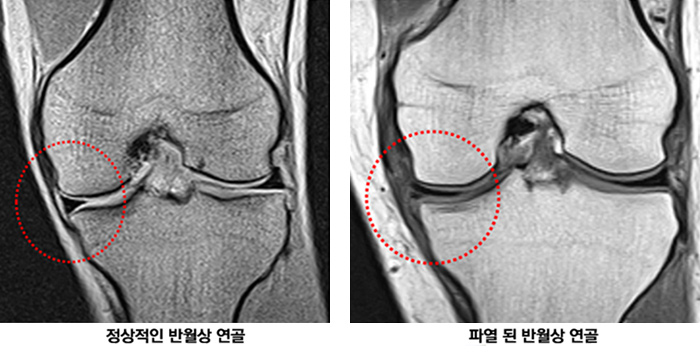

2. 슬관절 반월상 연골판-관절낭 파열의 자기공명영상 소견. MRI maging of the Meniscocapsular Tear of the Knee. 전철홍,박성규,정선관. 대한슬관절학회지 Year : 2001, Volume : 13, Nuber : 1 page: 74 ~ 78